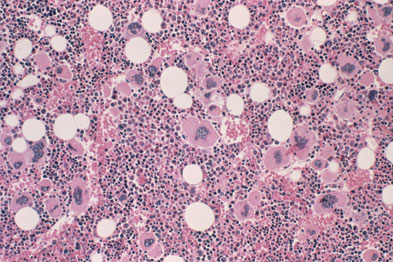

Can You Die From Myelofibrosis. This condition is in the bone marrow and negatively impacts blood cell production in the body. The average survival rate among myelofibrosis patients is five years following diagnosis. Myelofibrosis can cause your bone marrow to harden. The condition gradually changes bone marrow tissue into scar tissue, inhibiting the bone marrow’s ability to create new blood cells.

When myelofibrosis occurs on its own, it is called primary myelofibrosis. This condition is in the bone marrow and negatively impacts blood cell production in the body. This means that the patient will die eventually. The condition gradually changes bone marrow tissue into scar tissue, inhibiting the bone marrow’s ability to create new blood cells. Studies suggest that the incidence of primary myelofibrosis is equal for adults of any sex. The idea of myelofibrosis as a gift was deeply felt, sharpening perceptions, stripping away.

The idea of myelofibrosis as a gift was deeply felt, sharpening perceptions, stripping away. When that happens, the connective tissues that surround your bones become inflamed. In its end stages, myelofibrosis presents as a wasting illness with internal bleeding due to decreased platelet levels, liver failure and general disability, explains healthcentral. A retrospective study with a cohort of 109 individuals classified myelofibrosis into 4 stages, namely, mf0 (absence of reticulin fibrosis), mf1 (mild reticulin fibrosis), mf2 (overt collagen myelofibrosis) and mf4 (osteomyelosclerotic stage). The goal of this study was to examine if the presence of these risk factors were associated with cause of death (cod) in patients with myelofibrosis (mf). A process called allogenic stem cell transplantation is the only cure.

If it occurs as the result of a separate disease, it is known as secondary. In myelofibrosis, your stem cells don’t work like they should. I am only taking this chinese medicine for 3 months, it will take at lease 6 months. Individuals who have had exposure to certain chemicals, such as benzene and toluene, have a higher risk of developing myelofibrosis. A retrospective study with a cohort of 109 individuals classified myelofibrosis into 4 stages, namely, mf0 (absence of reticulin fibrosis), mf1 (mild reticulin fibrosis), mf2 (overt collagen myelofibrosis) and mf4 (osteomyelosclerotic stage).

A retrospective study with a cohort of 109 individuals classified myelofibrosis into 4 stages, namely, mf0 (absence of reticulin fibrosis), mf1 (mild reticulin fibrosis), mf2 (overt collagen myelofibrosis) and mf4 (osteomyelosclerotic stage). Individuals who have had exposure to certain chemicals, such as benzene and toluene, have a higher risk of developing myelofibrosis. The condition gradually changes bone marrow tissue into scar tissue, inhibiting the bone marrow’s ability to create new blood cells. Myelofibrosis can develop in people of any age, however, it is most commonly diagnosed in individuals who are aged about 50 to 60. In myelofibrosis, your stem cells don’t work like they should.